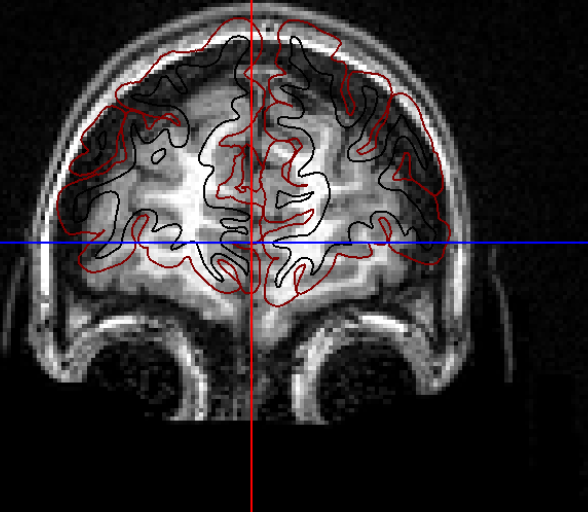

I’m using xcp_d for post-process the output from fmriprep. I found misalignment between t1w and atlas almost all the subjects, similar to the case here but with worse result:

Screenshots / relevant information: